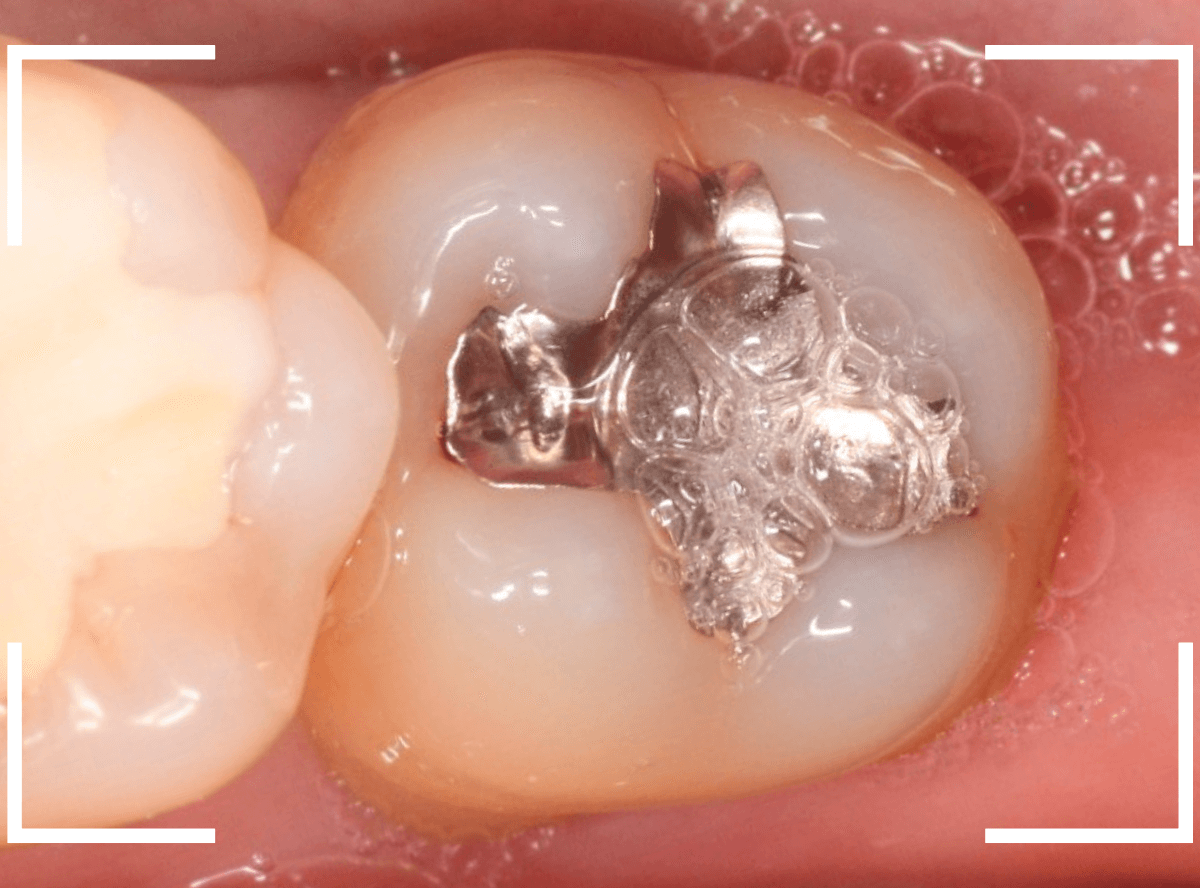

検診で、金属のつめ物のの中と、歯の側面に虫歯が見つかった方です。

まずは、手前(左)側の治療です。

こちらが、お口の中を見たところです。

〇部の中に虫歯があると思われます。

今回のように、金属のつめ物やレジン治療をしてある歯の側面の虫歯の診断はわかりづらく、難しいです。

金属のつめ物を外したところです。

この白いセメントの中に虫歯があると思われます。

セメントを除去したところです。

赤く染まっている部分が虫歯です。

真っ赤ですね(^^;)

慎重に虫歯を除去していきましたが、まだ薄く染まっています。

もう少し除去する必要があります。

全ての虫歯が取れました、かなり深い神経まで近い虫歯でした。

次に奥側(右側)の虫歯の治療に移ります。